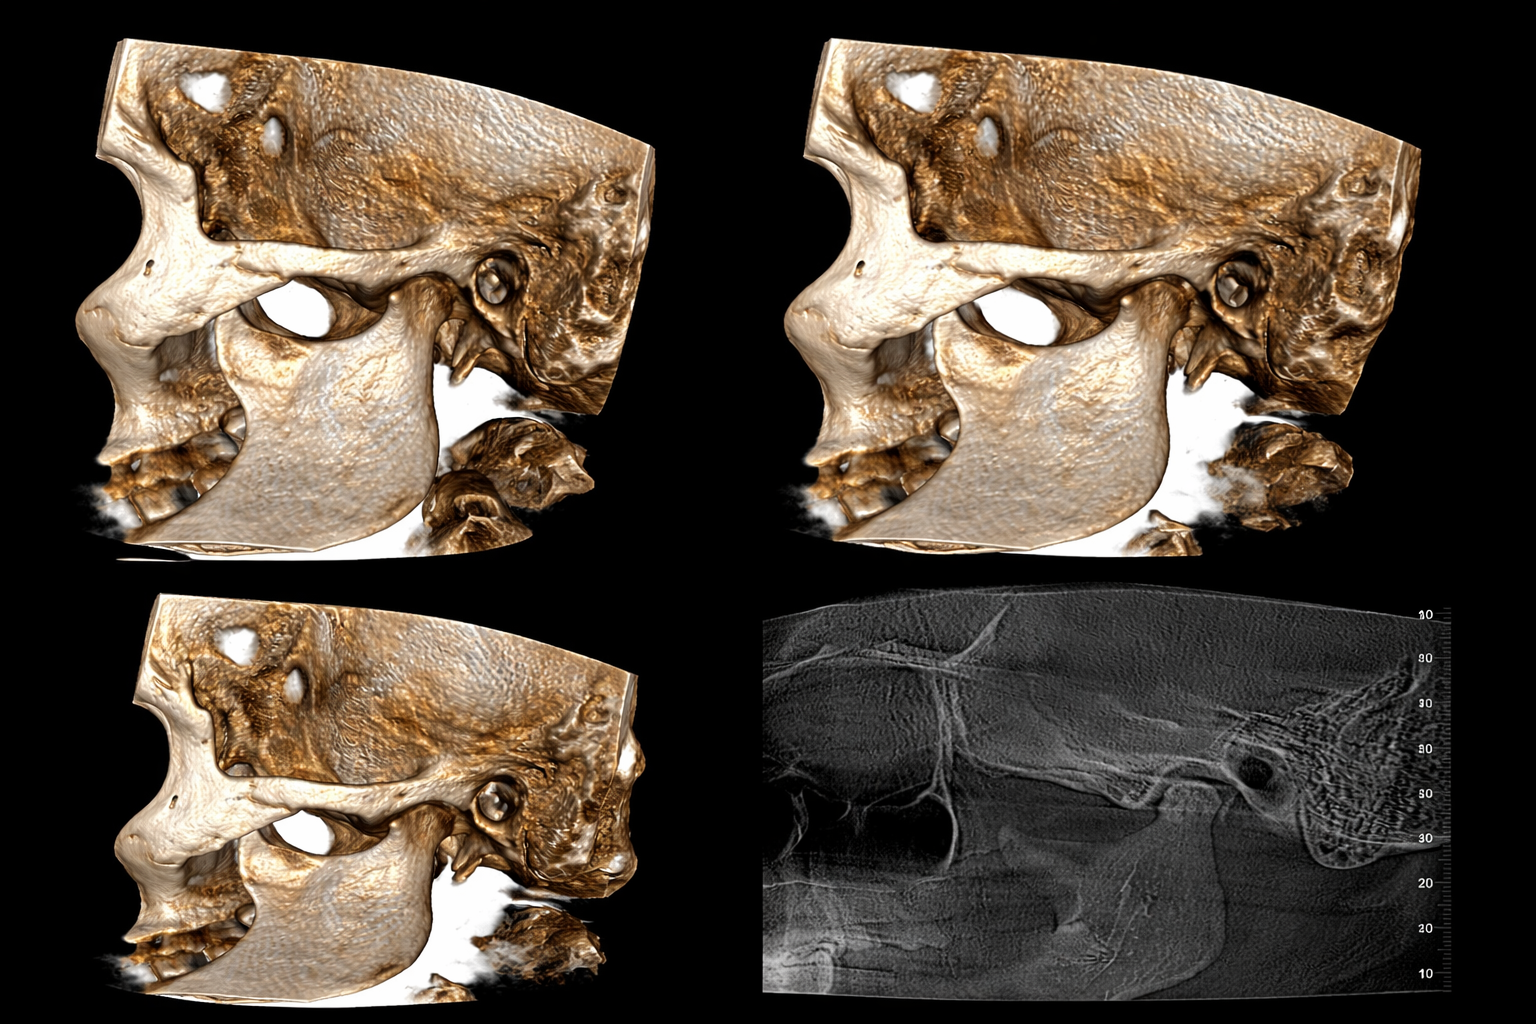

When it comes to advanced dental imaging, precision is not optional — it is essential for safe and successful treatment outcomes. A CBCT (Cone Beam CT) scan provides highly detailed 3D images of the teeth, jawbone, nerve pathways, and surrounding anatomical structures, allowing clinicians to make accurate, evidence-based decisions. At Insight Diagnostics & Lab, CBCT imaging is performed using advanced digital technology and reviewed with strict diagnostic protocols to ensure clinical accuracy for dental and maxillofacial evaluations in Pallavaram.

Unlike conventional dental X-rays that provide two-dimensional views, CBCT technology captures volumetric 3D data in a single, low-dose scan. This enables dentists, orthodontists, implantologists, and oral surgeons to assess bone density, sinus anatomy, impacted teeth, and nerve positioning with exceptional clarity and precision. If you are looking for a trusted 3D CBCT scan centre in Pallavaram, Insight Diagnostics & Lab delivers reliable imaging, standardized reporting, and patient-focused diagnostic care designed to support confident treatment planning.

Cone Beam Computed Tomography is a specialized imaging technology designed specifically for dental and facial bone evaluation. It uses a cone-shaped X-ray beam to capture multiple images in a single rotation, reconstructing them into a 3D digital model. This makes Cone Beam Computed Tomography in Pallavaram an essential diagnostic tool for complex dental procedures.

CBCT differs from conventional CT scans by delivering lower radiation exposure while providing high-resolution imaging of hard tissues. It is particularly useful for dental implant planning, impacted teeth analysis, TMJ assessment, cyst detection, and orthodontic treatment planning.

Dental implant success depends heavily on precise bone assessment. A 3D CBCT scan allows implantologists to measure bone height, width, and density accurately before placing implants.

It also helps in identifying nerve pathways and sinus cavities, reducing the risk of surgical complications. This makes Cone Beam Computed Tomography in Pallavaram an essential step in modern implant dentistry.

Orthodontic treatment planning requires precise evaluation of tooth position, jaw alignment, and underlying bone structure. A CBCT scan provides a complete three-dimensional view of impacted teeth, root angulations, and surrounding bone support, which cannot be accurately assessed using traditional 2D X-rays. This level of detail allows orthodontists to design safer and more predictable treatment plans.

In cases of impacted wisdom teeth or canines, CBCT imaging helps determine the exact location of the tooth in relation to adjacent roots and nerve canals. At Insight Diagnostics & Lab, our advanced Cone Beam Computed Tomography in Pallavaram supports orthodontists and oral surgeons with high-resolution imaging that improves diagnostic clarity and reduces surgical uncertainty.

Temporomandibular Joint (TMJ) disorders can cause chronic jaw pain, clicking sounds, restricted mouth opening, and facial discomfort. CBCT scanning allows detailed visualization of the jaw joint structure, including the condyle and surrounding bone components, helping clinicians detect structural abnormalities.

Unlike standard radiographs, CBCT provides cross-sectional and volumetric views of the TMJ, enabling early diagnosis of degenerative changes, joint misalignment, or bone erosion. For patients experiencing persistent jaw pain in Pallavaram, CBCT imaging plays a vital role in identifying the root cause and guiding appropriate treatment.

CBCT scanning has significantly advanced modern dentistry by enabling highly accurate, low-dose, and clinically reliable 3D imaging. From dental implant planning and orthodontic assessment to TMJ analysis and oral surgical evaluation, Cone Beam CT technology supports precise diagnosis and predictable treatment outcomes. The ability to visualize bone structure, nerve pathways, and anatomical variations in three dimensions allows dentists to minimize complications and improve long-term treatment success.